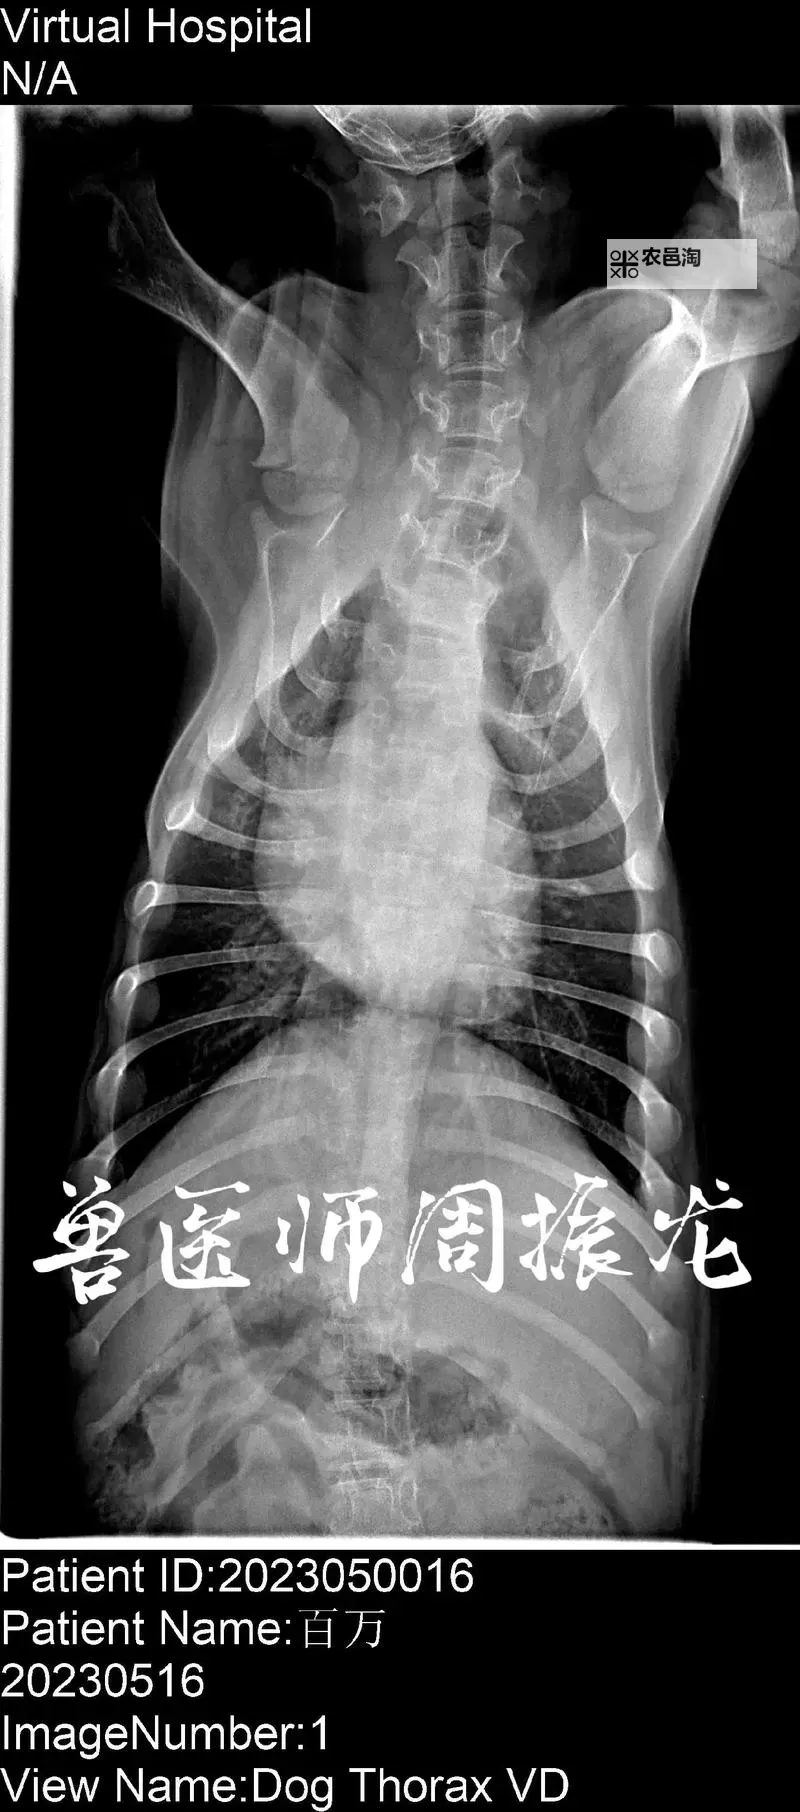

在实践操作中,正确的患者定位和呼吸指导也是确保曝光成功的要素。患者需站立或坐稳,双臂自然放置,双肩自然下垂,确保心胸和肺部区域无遮挡;同时,指导患者深呼吸并屏气片刻,可以增加肺野的清晰度,减少模糊和重影影像。此外,合理选择拍摄角度,例如正面位(PA)和侧位(LAT),也是保证影像质量的重要环节。每个细节都关系到最终的影像质量,而良好的标准操作规范则能最大程度降低错误率。